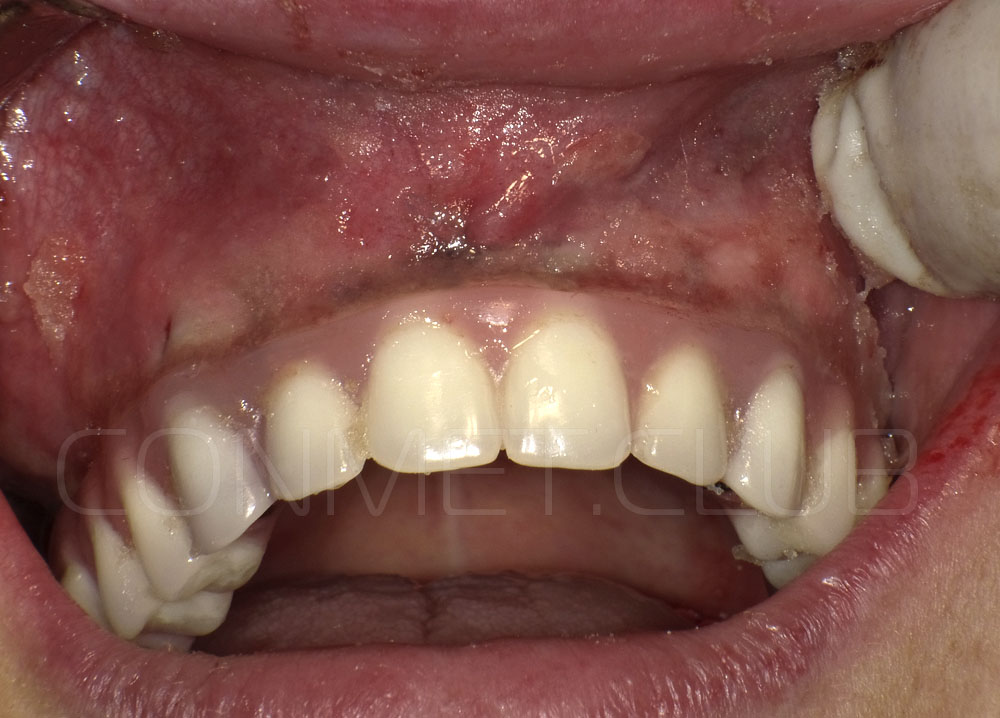

Новые, искусственные зубы фиксируются к этому имплантату стандартными, трансокклюзионными винтами на 1-14 день (в данном клиническом случае на 5 сутки) и по существу являются несъемными!

И в-четвертых: небольшой фрагмент из операции по восстановлению всех утраченных зубов на верхней челюсти. По сути эта операция полностью повторяет протокол и этапность операции представленной в первой части статьи, за исключением того, что искусственные зубы были зафиксированы сразу после операции. Со слов самой пациентки, процесс жевания был совершенно безболезненным с самого первого дня.